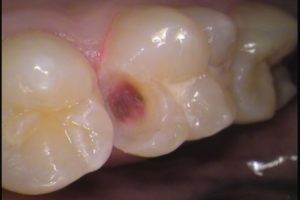

今回の治療は、右上6番目の歯です。

お口の中を見てみると、なにやら黒い所が、、、

本人は痛みなどの症状はないようです。

場所はわかりますか?

赤丸で囲まれたココです!

デコボコしているのですが、前に治療した形跡があり、

レジンで詰め物がされています。

その周囲から虫歯が入り込み、2次虫歯になってしまっています。